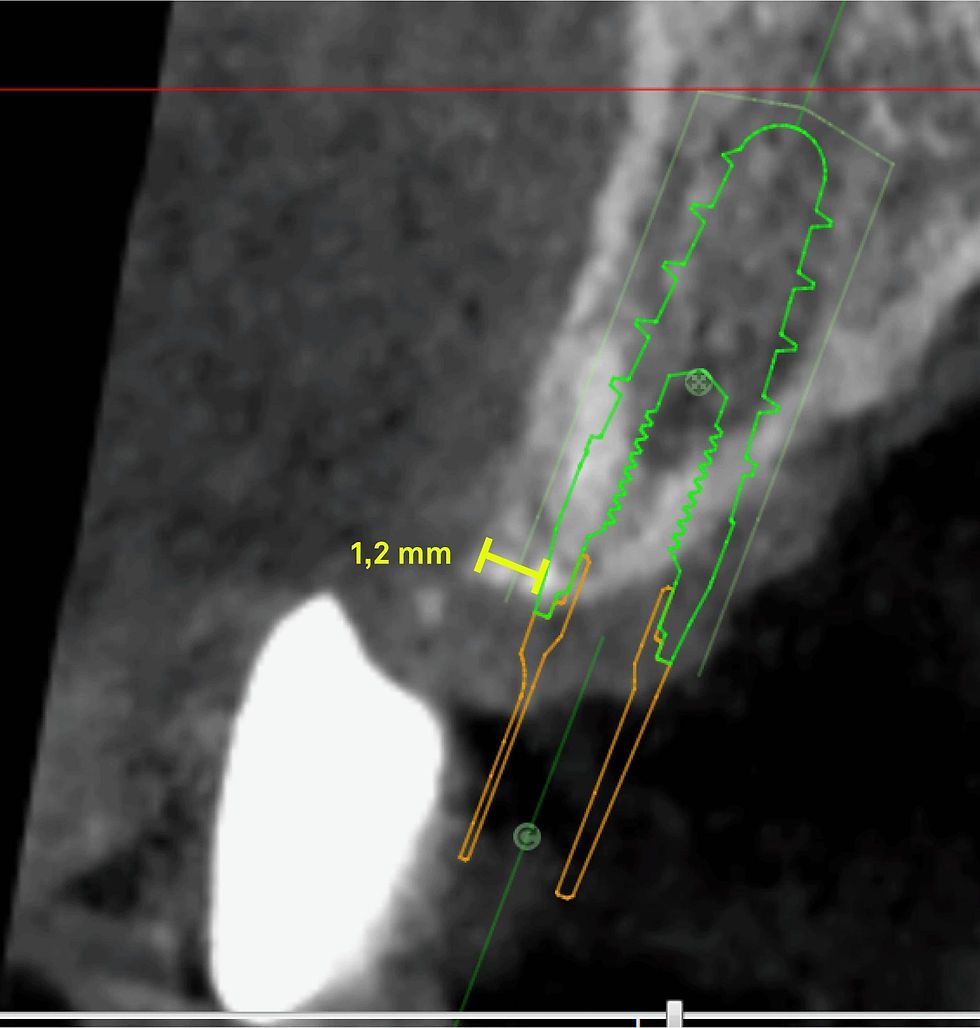

The poor vestibular bone thickness and the need to minimize surgical invasiveness lead to opt in favor of guided surgery to insert a Prama RF implant. The choice to leave the palatal portion of the intramucosal neck in contact with the soft tissues is due to the desire to preserve as much as possible the thickness of the residual vestibular bone wall, so as to guarantee a good vascularization to the tissue that will cover it.

Radiographs and CBCT of the Prama RF implant inserted via guided surgery. The comparison between the plan and CBCT confirms the precision and the correct execution of the implant positioning.